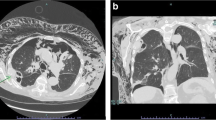

Pneumothorax. a The transducer is placed in a longitudinal axis over an intercostal space at the anterior surface of the chest; this is the area where free air in the chest cavity is expected to be located. b If pneumothorax is present the pleura-line only represents the parietal pleura, therefore the motion of the visceral pleura cannot be visualised and subsequently lung sliding is absent. c In M-mode the lack of lung sliding will appear as the “stratosphere sign”, a pattern only consisting of horizontal lines